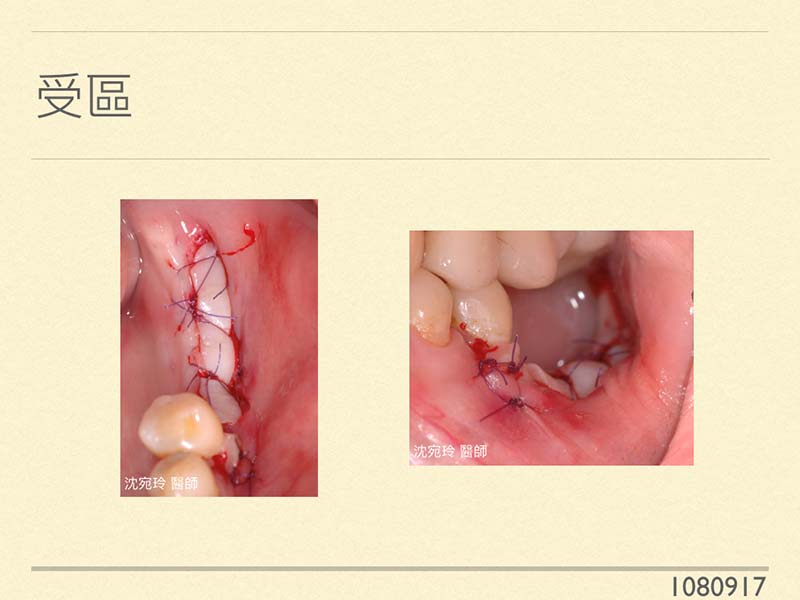

一般來說,手術切線處(就是將來縫合處),左右的皮瓣要至少需有 2-3mm寬。醫師在頰側進行大型補骨時,如果縫合後縫線位置落在太偏舌側,則舌頭在移動時亦容易造成傷口裂開,而降低植牙補骨成功率。因此,為了提高植牙補骨手術成功率,同時希望將來植牙接出假牙之後,植牙周邊能有3-5mm的角質化上皮,在補骨前「先做一次」「角質化上皮移植手術」是必要的!

病患在臨床觀察,角質化上皮十分缺乏,同時以手術模板評估將來植牙的位置,發現頰側骨缺損十分大量,若要做一次成功的補骨手術,以現況來說就容易在術後腫脹時,組織斷裂,而使補骨成功率下降。因此,為了長久成功率著想,我們做了『植牙前的角質化上皮移植術』;而這次的手術,我們同時照顧了植牙旁的自然牙,進行了牙根覆蓋術。病患術後的的迴響良好,只吃了一天的止痛藥,日常生活一切正常喔!因為我們知道如何手術才能減少疼痛、減少出血、快速癒合、增加成功率,您所想到的每一項都是我們在乎的!